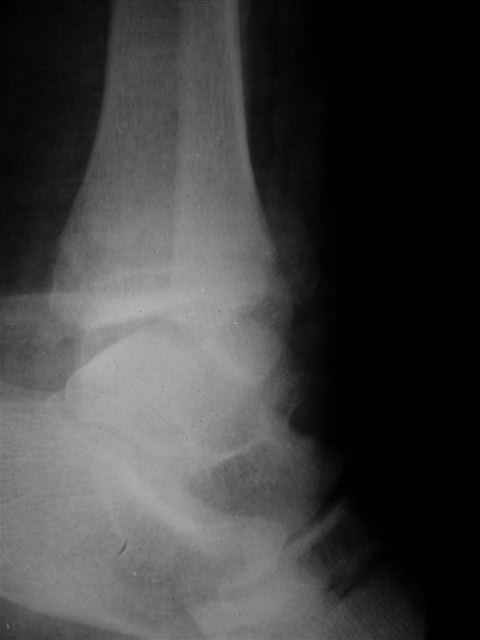

Re: открытый перелом мыщелков бедра, латерального

Я предупреждал, что ничего сверхъестественного. Каюсь, что одна из спиц прошла несколько дальше, чем нужно было, но главное - перелом стабилизирован и больной работает суставом в полном объёме, несмотря на представленную раннее травму коленного сустава.